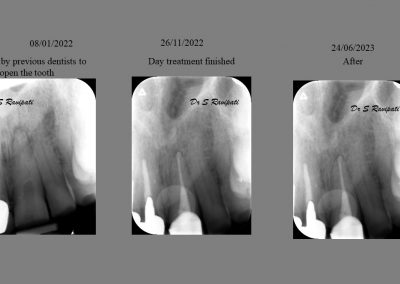

During the consultation, the dentist will first listen to your concerns and carry out appropriate tests to identify the right tooth that is causing pain. As a part of the diagnosis, your dentist will carry out various clinical tests to identify the right tooth and will take some radiographs which can aid in the diagnosis.

An access cavity is placed on the surface where the patient bites, to reach the root canals of the tooth. Once all the canals are identified, small files are used to remove the infected pulp.

Files of different sizes are used to eliminate bacteria and infection and to shape the canals. The canals are disinfected thoroughly with irrigants and later the canals will be sealed in 3 dimensions with a special medicament called gutta-percha to prevent reinfection of the tooth and the access cavity will be sealed with a temporary filling.

After a few weeks, the tooth will be checked and when all the infection has cleared, a crown will be usually required to protect the restore the tooth to function.

Studies have shown thorough cleaning with instruments, disinfection and sealing the canals contribute to the successful healing of the infection and this success is reported as 95%.